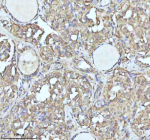

Immunohistochemical staining of IDH3B using anti-IDH3B antibody. IDH3B was detected in a paraffin-embedded section of follicles of human thyroid cancer tissue. Heat mediated antigen retrieval was performed in EDTA buffer (pH 8.0, epitope retrieval solution). The tissue section was blocked with 10% goat serum. The tissue section was then incubated with 2 ug/ml rabbit anti-IDH3B antibody overnight at 4oC. Peroxidase Conjugated Goat Anti-rabbit IgG was used as secondary antibody and incubated for 30 minutes at 37oC. The tissue section was developed using an HRP secondary and DAB substrate.